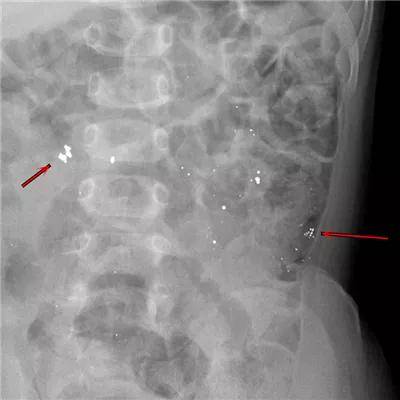

6岁·磁力珠

5小时前不慎误服磁力珠,未见呕吐,无腹痛。

2岁·磁力珠

1天余前误吞磁力珠9颗,每颗直径2mm左右,误服时孩子主诉食管部位不适。

单个磁铁的危险性不大,但是多个磁铁进入体内后,在不同的消化道会紧紧地吸在一起,强烈的吸力会导致消化道穿孔。